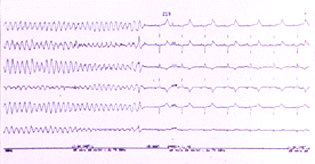

Se ha reportado un caso de taquicardia ventricular intermitente en un feto durante la gestación , cuya madre sufre de síndrome de QT largo (29) , posterior al nacimiento el bebe evidencio la presencia de QT largo. En un importante estudio Shwartz y col (30) analizaron 333034 ECG tomados entre el tercer y cuarto día de vida de recien nacidos entre los años 1976-94 para medir el QT y realizaron el seguimiento al año. Durante este período ocurrieron 34 muertes: 24 por muerte subita infantil , de los cuales 12 presentaban QTc de mayor duración que los que murieron por otras causas (435+/- 45 mseg vs 393 +/-24 mseg) o que el grupo sobreviviente (400 +/- 20 mseg) . Ninguno de los casos que sobrevivieron o que fallecieron por otras causas presentaban QT largo . El riesgo relativo de muerte súbita infantil con QTc > 440 mseg es de 41.3 (95 % intervalo confidencia 17.3 a 98.4) lo cual, es mucho más elevado que el producido por los factores clásicos como la madre fumadora. En teoría los niños con SQTL podrían beneficiarse con la administración cuidadosa de betabloqueantes. Hofbeck y col (31) sugieren que la presencia de bradicardia en un feto sin otra evidencia de patología cardíaca deberá hacer sospechar de SQTL , debiendo realizarse ECG y valoración completa familiar en estos niños.